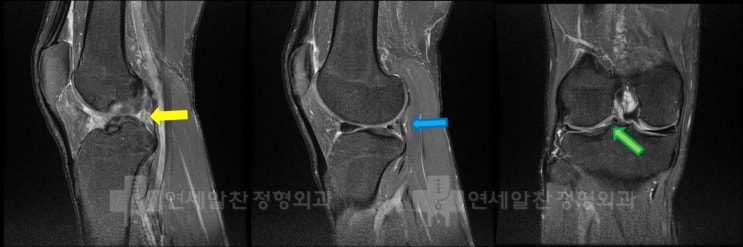

슬관절 통증의 진단에서 history taking, 이학적 검사의 중요성

50세 여자환자가 무릎 통증을 주소로 내원하였다. 환자는 2개월전 턱에 걸려 넘어지면서 무릎이 꺽이면서 ...